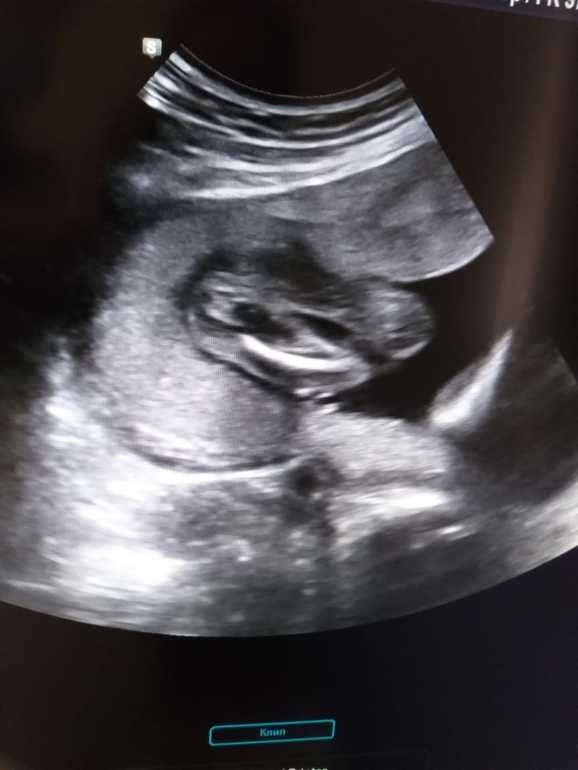

Пол малышаделала узи в 19 недель.сказали девочка. но как то неуверенно.мечтаю о дочке.может кто то подскажет по УЗИ пол?